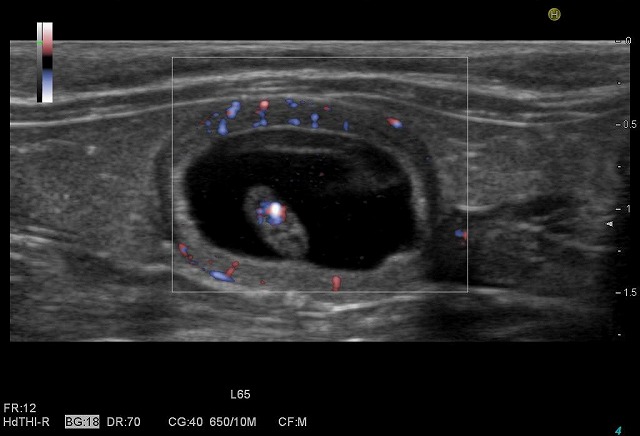

カラードプラ検査で、胎児の心臓の中の血流が赤青に色が付いて見えます。

胎児を包んでいる胎盤の中の血液の流れも赤青に色が付いて見えます。

約4mmの胎児の体の中の心臓が、力強く脈打っているのがよくわかります。

超音波検査機器を「HI VISION AVIUS」という高性能な機種に変更したことで、さらに精密な検査ができるようになりました。